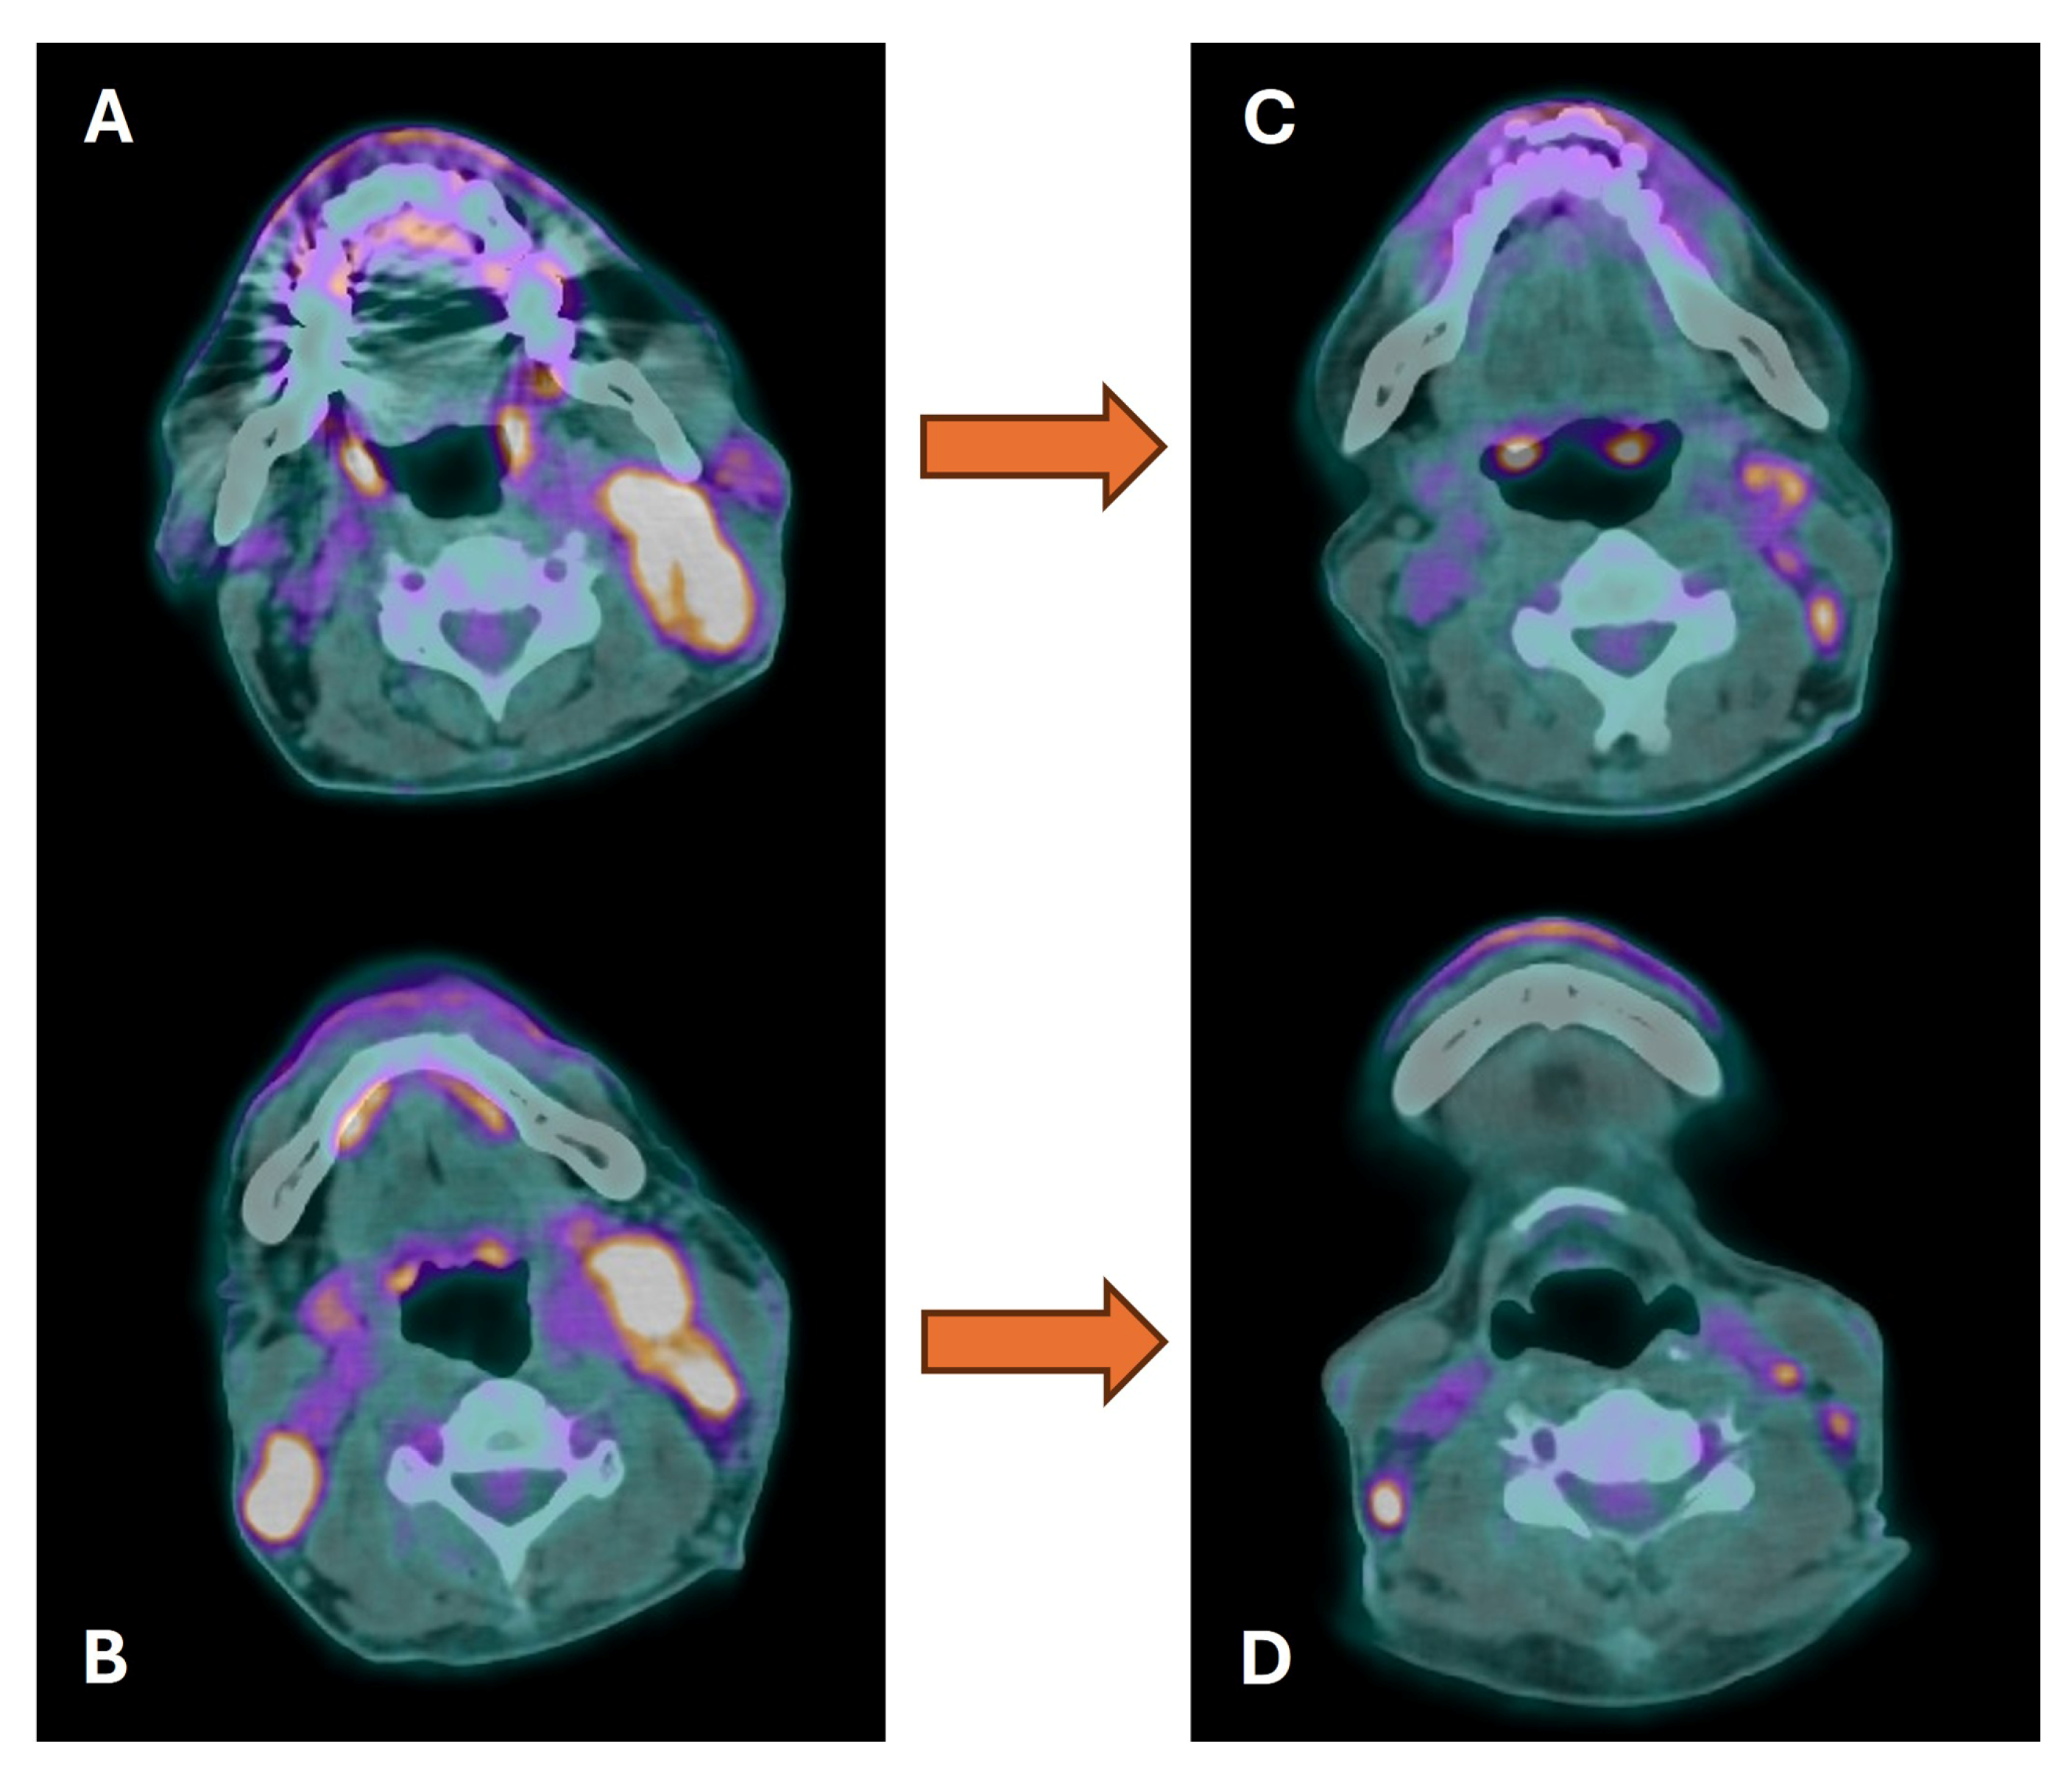

3.3. Distant Metastasis Assessment

3.4. Second Primary Tumor Assessment

- Johansen, J.; Buus, S.; Loft, A.; Keiding, S.; Overgaard, M.; Hansen, H.S.; Grau, C.; Bundgaard, T.; Kirkegaard, J.; Overgaard, J. Prospective study of 18FDG-PET in the detection and management of patients with lymph node metastases to the neck from an unknown primary tumor. Results from the DAHANCA-13 study. Head Neck 2008, 30, 471–478. [Google Scholar] [CrossRef] [PubMed]

- Han, A.; Xue, J.; Hu, M.; Zheng, J.; Wang, X. Clinical value of 18F-FDG PET-CT in detecting primary tumor for patients with carcinoma of unknown primary. Cancer Epidemiol. 2012, 3, 470–475. [Google Scholar] [CrossRef]

- Barbosa, M.; Duarte, H.; Breda, E.; Monteiro, E. PET/CT in the management of metastatic cervical lymphadenopathy from unknown primary site: A seven years retrospective study. Rev. Laryngol. Otol. Rhinol. 2013, 134, 89–94. [Google Scholar]

- Deonarine, P.; Han, S.; Poon, F.W.; de Wet, C. The role of 18F-fluoro-2-deoxyglucose positron emission tomography/computed tomography in the management of patients with carcinoma of unknown primary. Scott. Med. J. 2013, 5, 154–162. [Google Scholar] [CrossRef] [PubMed]

- Sekine, T.; Barbosa, F.G.; Sah, B.R.; Mader, C.E.; Delso, G.; Burger, I.A.; Stolzmann, P.; Ter Voert, E.E.; von Schulthess, G.K.; Veit-Haibach, P.; et al. PET/MR Outperforms PET/CT in Suspected Occult Tumors. Clin. Nucl. Med. 2017, 42, e88–e95. [Google Scholar] [CrossRef] [PubMed]

- Ruhlmann, V.; Ruhlmann, M.; Bellendorf, A.; Grueneisen, J.; Sawicki, L.M.; Grafe, H.; Forsting, M.; Bockisch, A.; Umutlu, L. Hybrid imaging for detection of carcinoma of unknown primary: A preliminary comparison trial of whole-body PET/MRI versus PET/CT. Eur. J. Radiol. 2016, 85, 1941–1947. [Google Scholar] [CrossRef] [PubMed]